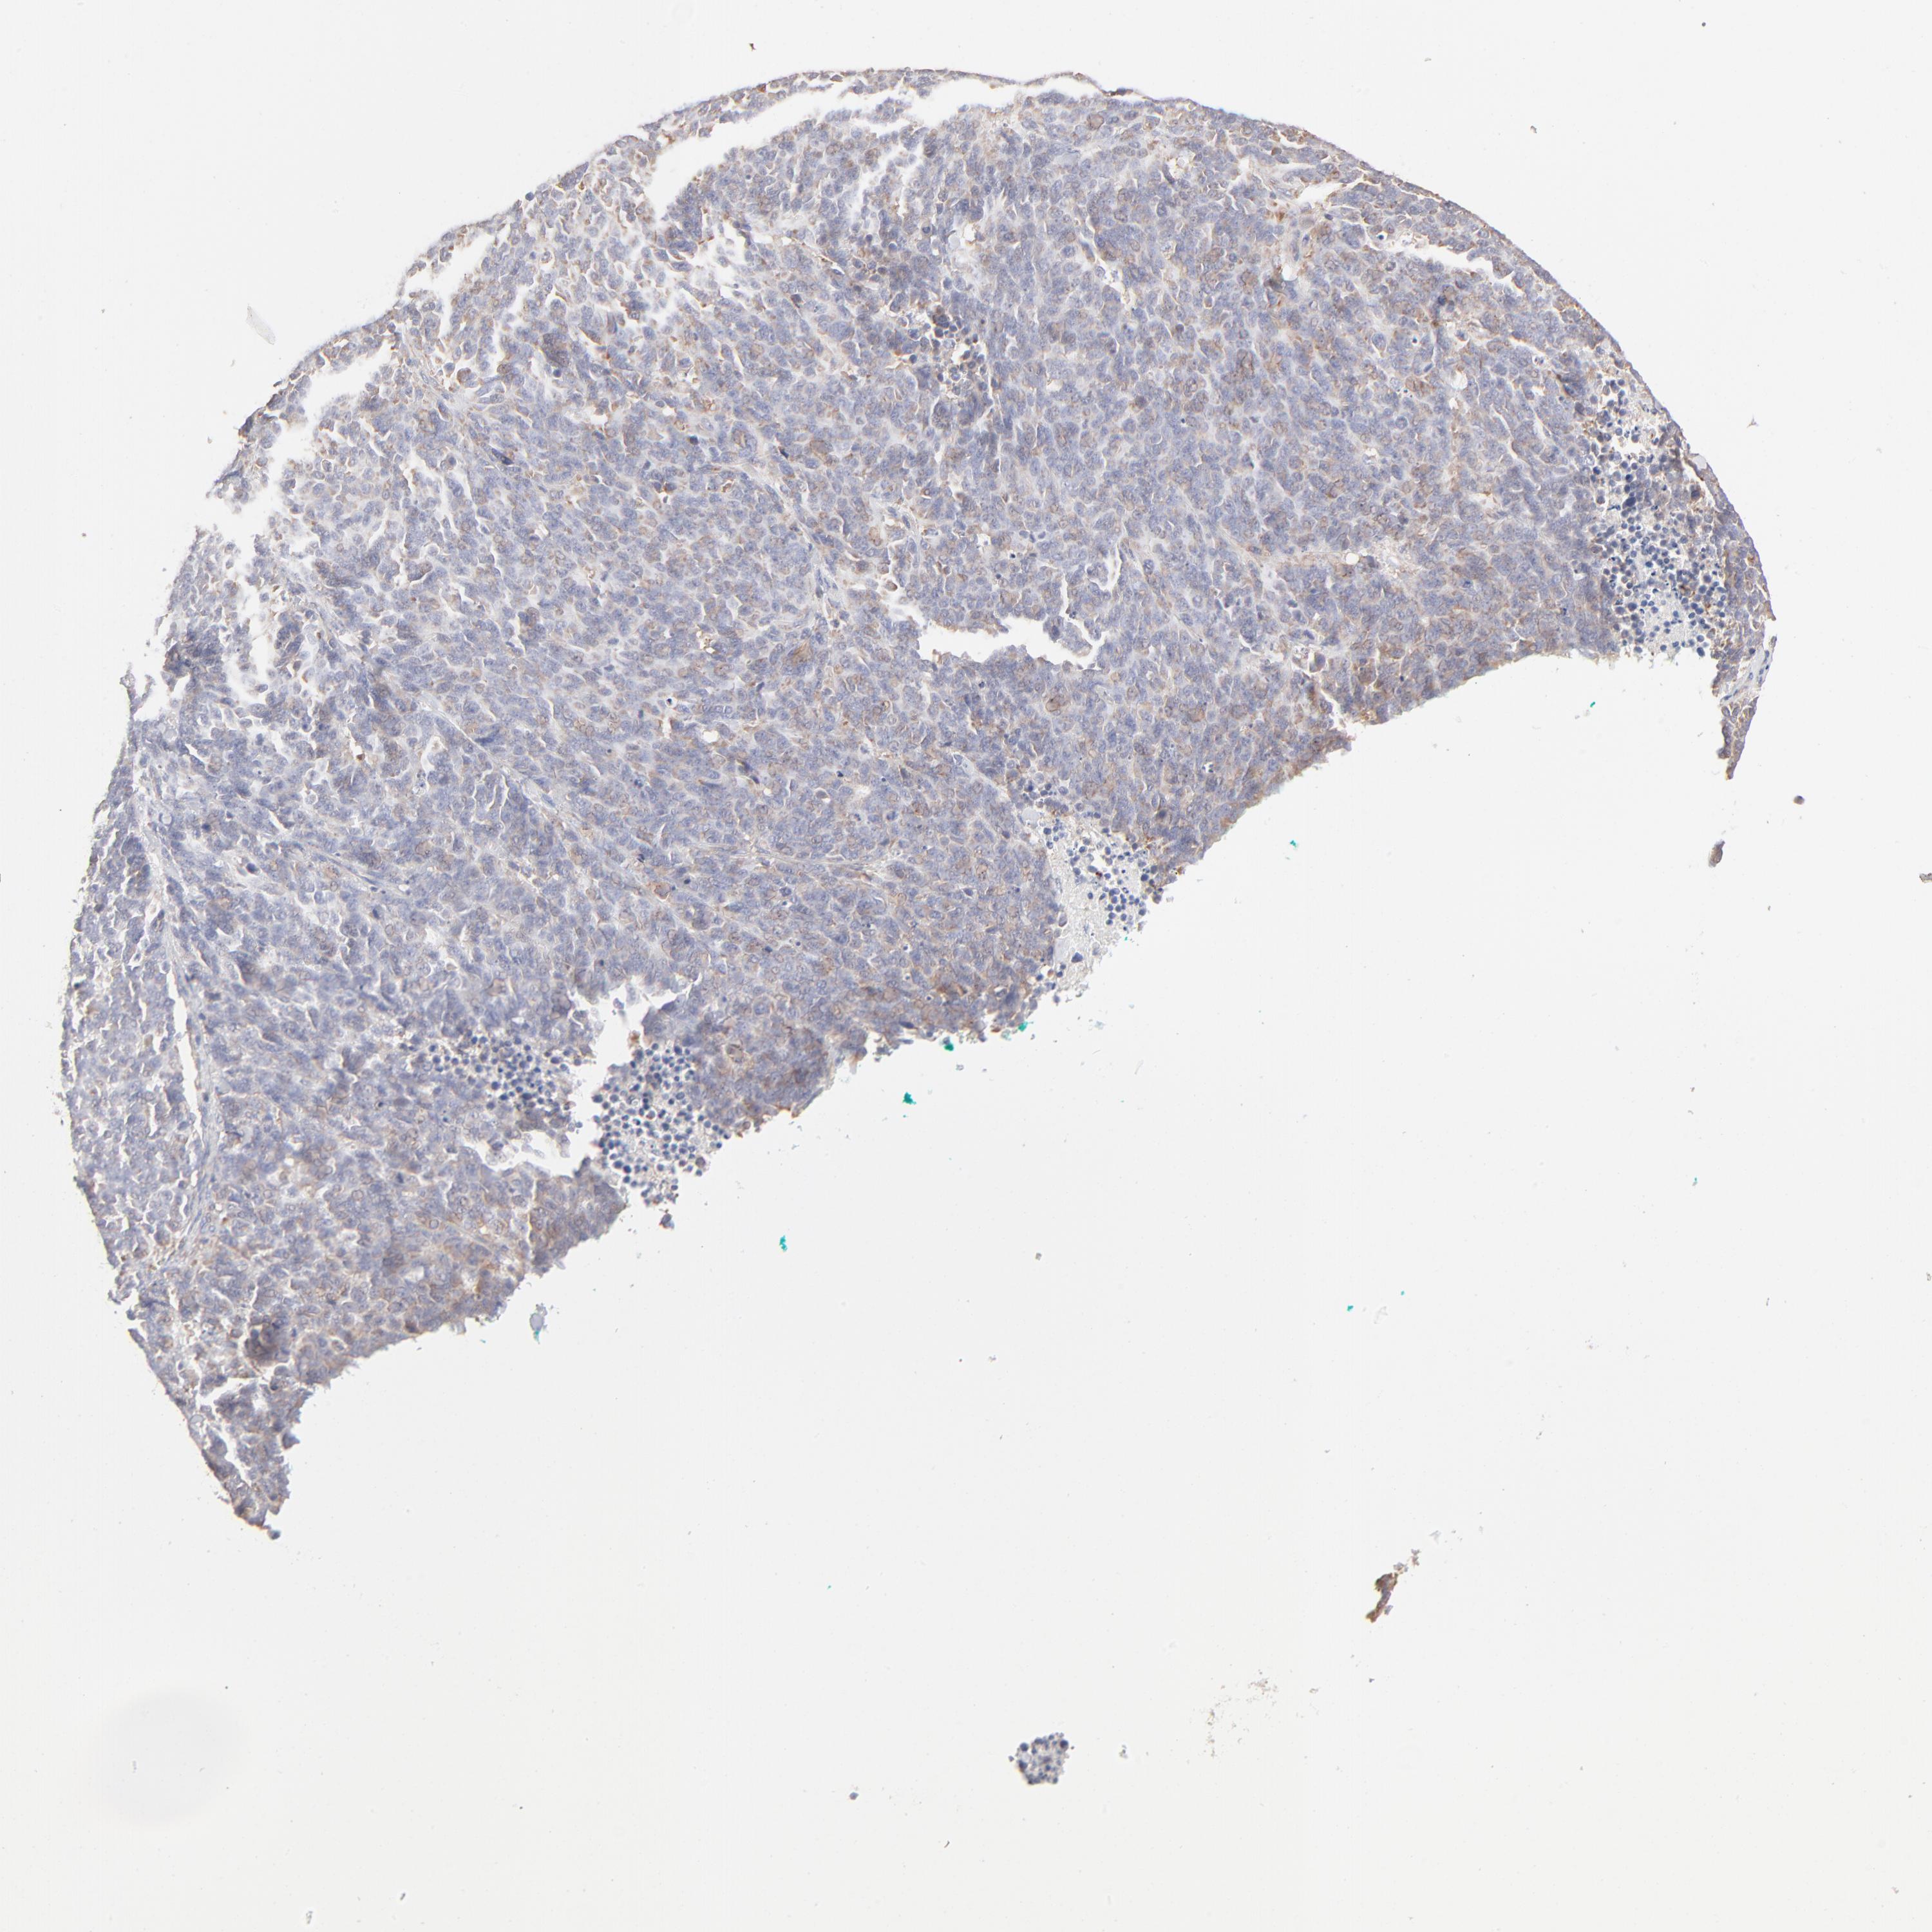

LUNG SQUAMOUS CELL CARCINOMA (TCGA) - Interactive survival scatter ploti

The Survival Scatter plot shows the clinical status (i.e. dead or alive) for all individuals in the patient cohort, based on the same data that underlies the corresponding Kaplan-Meier plots. Patients that are alive at last time for follow-up are shown in blue and patients who have died during the study are shown in red.

The x-axis shows the expression levels (FPKM) of the investigated gene in the tumor tissue at the time of diagnosis. The y-axis shows the follow-up time after diagnosis (years). Both axes are complimented with kernel density curves demonstrating the data density over the axes. The top density plot shows the expression levels (FPKM) distribution among dead (red) and alive patients (blue). The right density plot shows the data density of the survived years of dead patients with high and low expression levels respectively, stratified using the cutoff indicated by the vertical dashed line through the Survival Scatter plot. This cutoff is automatically defined based on the FPKM cutoff that minimizes the p-score. The cutoff can be changed by dragging the vertical line or by entering a cutoff value in the square labeled "Current cut-off".

Under the Survival Scatter plot the p-score landscape (black curve; left axis) is shown together with dead median separation (red curve; right axis). Dead median separation is the difference in median mRNA expression between patients who have died with high and low expression, respectively. It is calculated as follows: median FPKM expression of dead patients with high expression - median FPKM expression of dead patients with low expression. This is intended to aid the user in visually exploring custom cutoffs and the associated p-scores and dead median separation.

Individual patient data is displayed and can be filtered by clicking on one or more of the category buttons on the top of the page. Categories describing expression level and patient information include: high, low, alive, dead, female, male and tumor stages. The scale of the x-axis can be toggled between linear and log-scale by clicking on the "x log" button. Mouse-over function shows TCGA ID, patient information and mRNA expression (FPKM) for each patient.

& Survival analysisi

Kaplan-Meier plots summarize results from analysis of correlation between mRNA expression level and patient survival. Patients were divided based on level of expression into one of the two groups "low" (under cut off) or "high" (over cut off). X-axis shows time for survival (years) and y-axis shows the probability of survival, where 1.0 corresponds to 100 percent.

RPS21 is not prognostic in Lung Squamous Cell Carcinoma (TCGA)

: 3433.05

P scorei

N/A

Average pTPM 2940.9

Number of samples 489